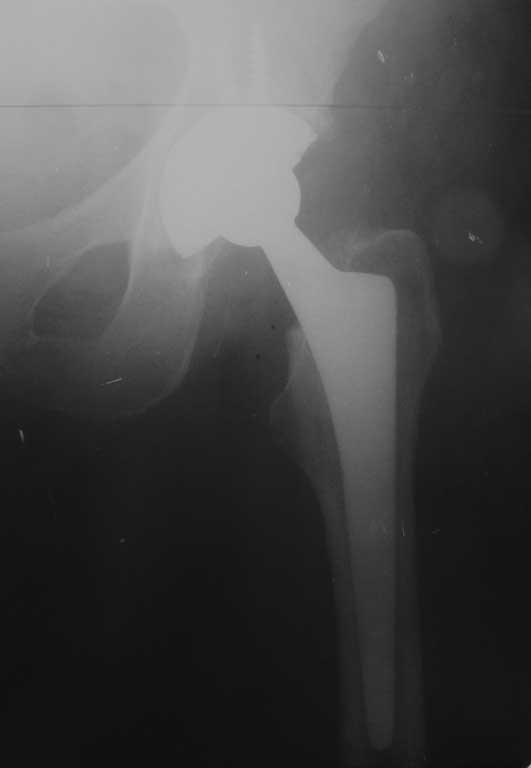

Уважаемые коллеги. Помогите определиться с тактикой лечения при перипротезном переломе бедра. Женщина 58 лет, ранее (в марте 2010г.) оперирована в нашем отделении по поводу перелома шейки бедра. Выполнено эндопротезирование сустава бесцементным протезом Зиммер (чашка Трилоджи и ножка Споторно). До получения последней травмы пациентка чувствовала себя хорошо: ходила не хромая , болей не было. 28.12.11 упала на улице. На рентгенограммах имеется перипротезный перелом бедра в верхней трети, проседание ножки протеза. Помогите с выбором тактики лечения. Наше мнение : ревизовать ножку на более длинную, предварительно выполнить остеосинтез бедра серкляжами. Вот только какую ножку выбрать: цементную или безцементную, Вагнера или Гелио (биомет) или длинную цементную ножку Экзетер(Страйкер). Всем спасибо.Всех с наступающим Новым Годом!!!

Уважаемый Сергей, нужна ножка Вагнера, а уже к ней Вы фиксируете фрагменты проксимального отдела серкляжами, так проще и надежней.

Уважаемый Сергей, необходима замена ножки на ножку типа Вагнера 190 или 225 мм, а фрагменты проксимального отдела фиксируете серкляжами. Это обычная практика в нашей клинике